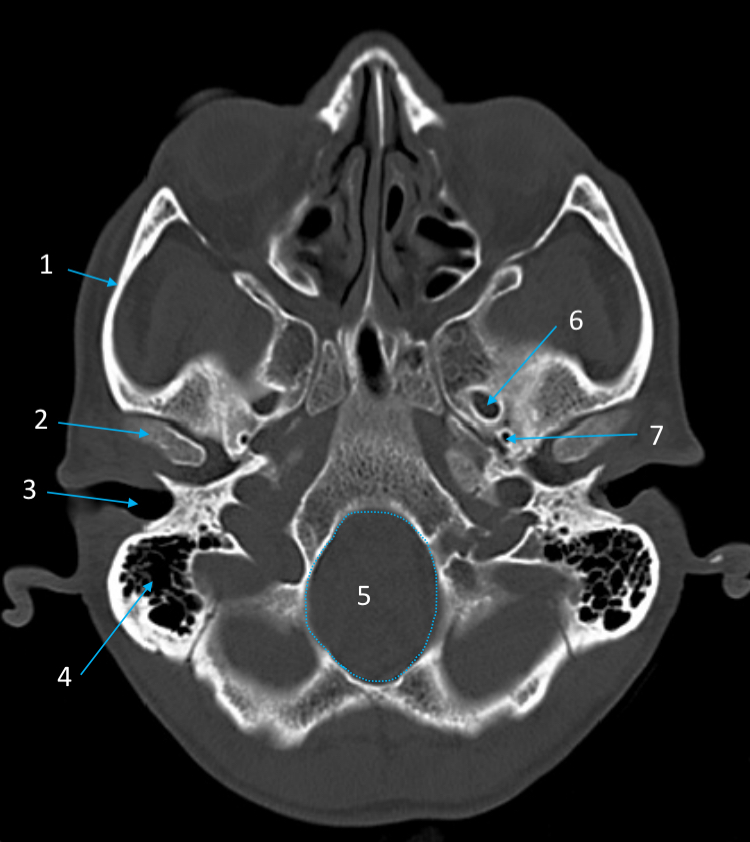

Mandible

ID bone

Maxilla

ID bone

Frontal sinus

ID structure

Pituitary fossa

ID structure

Occipital

ID bone

Lambdoid suture

ID structure

Frontal sinus

ID structure

Orbital margin

Orbit

Maxillary sinus

ID structure

Mandibular condyle

ID structure

Inferior nasal concha

ID structure

Hard palate

ID strucutre

Gonial angle

ID strucutre

Petrous ridge

ID structure

Groove of middle meningeal a.

ID structure

Roof of orbit

ID structure

Frontal sinus

ID structure

Pituitary fossa

ID structure

Petrous ridge

ID structure

Sphenoid sinus

ID structure

Hard palate

ID structure

Mastoid air cells

ID structure

Zygomatic arch

ID structure

Mandibular condyle

ID structure

External auditory meatus

ID structure

Mastoid air cells

ID structure

Foramen magnum

ID structure

Foramen ovale

ID structure

Foramen spinosum

ID structure